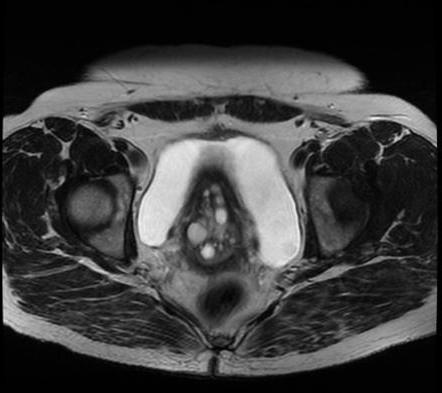

Ультразвуковое исследование с применением полостных датчиков – кисты шейки матки определяются как анэхогенные включения округлой или овоидной формы. Они могут быть как единичными, так и множественными. Чаще всего кистозные образования располагаются в эндоцервиксе, но встречаются и кисты стромы шейки матки. Внутренняя структура кист чаще однородная и анэхогенная, но иногда встречается неоднородное мелкодисперсное или гиперэхогенное содержимое с неровными контурами. Это связано с тем, что кисты возникают при нарушении оттока секрета желез, расположенных не только в слизистой оболочке цервикального канала, но и в мышечном слое. При цервикальном расположении кисты внутреннее содержимое кист не содержит сосудов. Усиление сосудистого рисунка в примыкающей строме не отмечается.

- УЗИ. Показано для определения размеров и локализации кистозных полостей. Киста видна как утолщение или уплотнение цервикального канала;